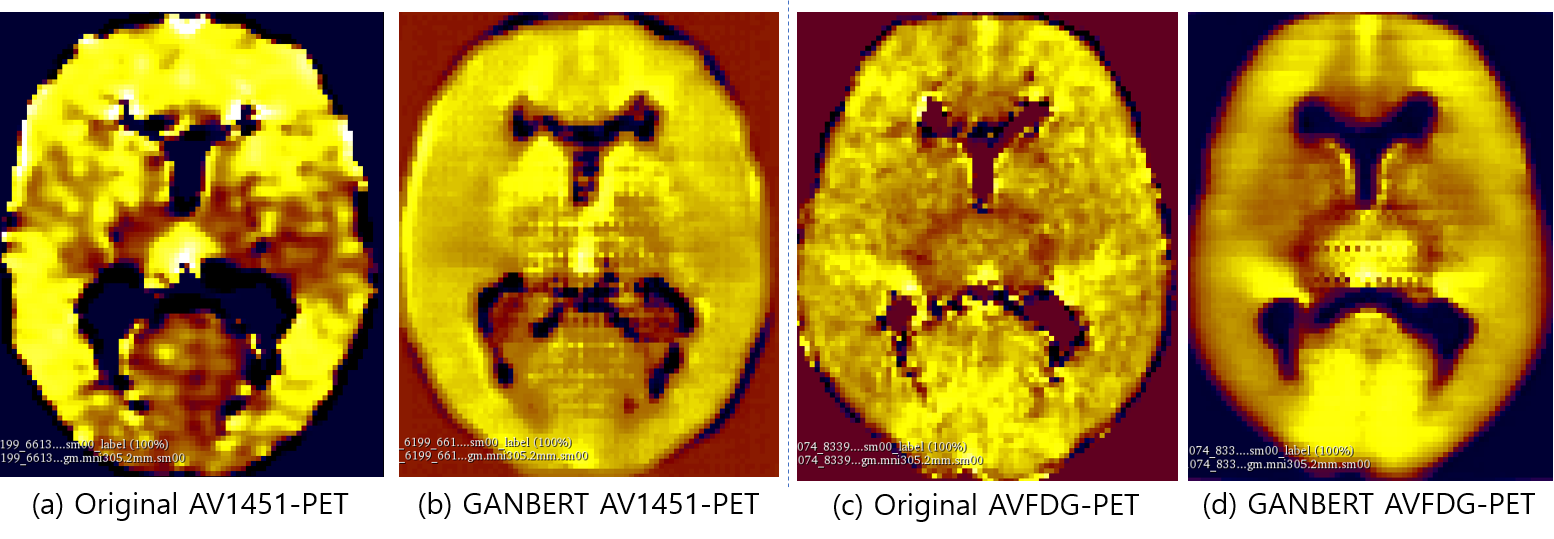

Refer to caption

Figure 5: Examples of AV1451 and FDG (a, c) PET and GANBERT synthesized (b, d).

5.2 Visual Examples of Generated PET Images

Examples of AV45-PET images generated by GANBERT and pix2pix are compared with the original PET image in Figure 1. GANBERT manages to generate close to the original AV45-PET image while pix2pix fails to generate a reasonable image. Some more examples of AV1451- and FDG- PET images generated by GANBERT are compared with the original PET images in Figure 2. Overall, images to close to the original PET images are generated by GANBERT in all three PET imaging techniques tested. The image quality of the center of the brain region is not as good as the other region, and it is suspected due to (1) differences in MRI and PET images, and (2) lack of training data.